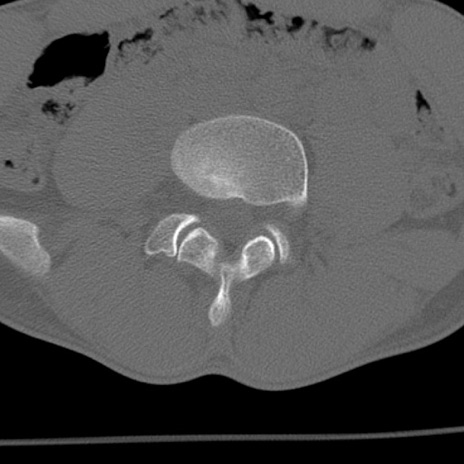

症例3 腰椎CT(横断像)

腰椎CT